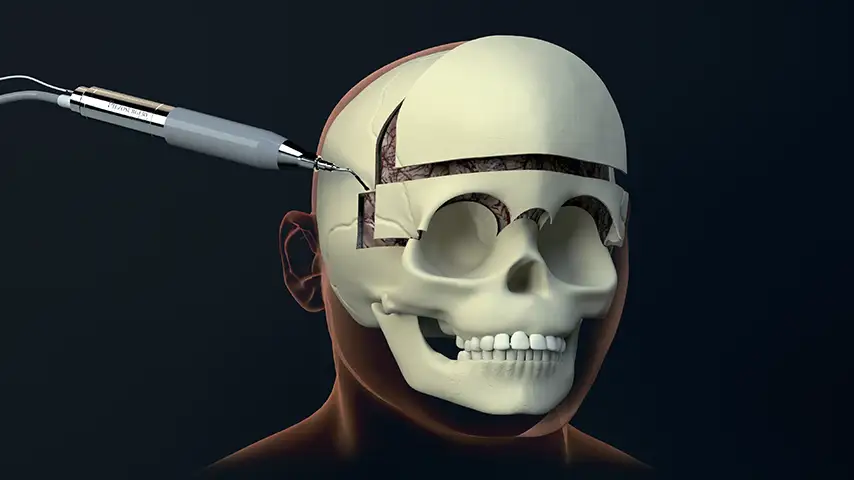

Craniotomy

and craniectomy

Reduced risk of CSF leak, better aesthetic result for the patient, sparing of fixation materials, dural and bone substitutes, due to selective and precise cutting.

Reduced heat ensures improved ossification with implants.

Selective cut preserves soft tissue. (Dura, neves and vessels)

Micrometric cut for minimal bone loss